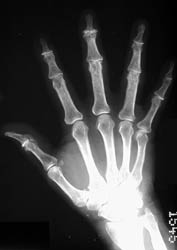

Primary osteoarthritis of the hands typically targets the PIP, DIP,

scaphotrapeziotrapezoid and the 1st carpometacarpal joints. The knee, hip,

spinal, and 1st metatarsophalangeal joints are other areas which are commonly

involved. Additional joints can be affected in cases of secondary osteoarthritis.

Radiographic Findings: Affected joint spaces are narrowed with reactive

subchondral sclerosis (eburnation). Other classic radiographic findings include

osteophytes and subchondral cysts. Heberden's nodes at the DIP joints and

Bouchard's nodes at the PIP joints of the hands are areas of osteophyte formation

and soft tissue swelling associated with osteoarthritis. Intraarticular loose

bodies can also sometimes be seen. Erosive osteoarthritis is an inflammatory

arthritis primarily seen in peri- and post-menopausal women; the distribution

pattern in the hands is the same as in primary osteoarthritis. However, this

process is associated with osteoporotic changes and erosions at the center

of the involved articular surfaces which create a "gull-wing" deformity.